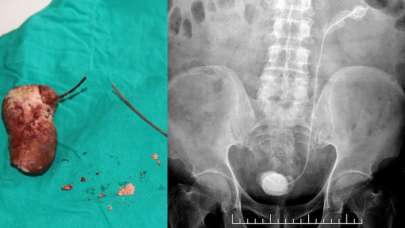

Unutkanlığın böylesi! 7 yıl boyunca içinde kalmış

6 yıl önce